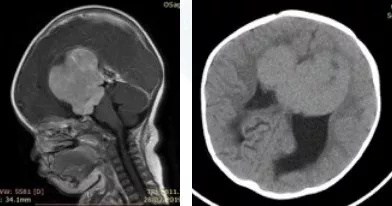

鞍区胶质瘤案例:刚满1岁的宝宝还没来得及长大,却就要匆匆离世。对一周岁脑内较大胶质瘤患儿小晴(化名)的父母来说,再没什么比这更痛心、残忍的事儿了!

“肿瘤位置较深,孩子年龄太小,脑瘤太大,手术风险很高,切除率不高,且术后较大可能出现失明……”辗转托付熟人朋友挂专家号,问诊过很多国内大医院的神经外科医生,得到的说法如出一撤。

03 跨越大洋的咨询方案

INC三位海外儿童神外专家在看过小晴的情况后,得出了总体上比较一致的咨询建议--患儿很可能为鞍区视神经胶质瘤,这通常是低级别或良性肿瘤,且治愈率较高。这种低级别胶质瘤优选的治疗方法是完全完全地手术切除,这对于解除大脑的局部压力重要,但同样也要面临手术所承担的风险,包括垂体功能不全、视力障碍和中风等。如果能够大水平顺利切除,则预后生存率会好,不会干扰正常的生活,后续持续跟踪及接受适当的治疗,则可与一般人寿命相似,但对于复发率的评估需要根据肿瘤的级别及性质决定。

04 “手术切除率有望达到90%甚至以上”

对于手术切除程度,INC三位海外儿科专家都有着比较明确的评估,一般都能达到80%以上的切除率,在这方面巴特朗菲教授具有丰富的经验,对小晴的案例甚至能达到90%乃至更高的切除率,在他的一系列临床病例中证明了?量全切/次全切除的可能性与良好的功能结果有关。手术过程中的风险与肿瘤的?管特征有关,因为婴?年龄很?,血液储备有限,这需要仔细的?醉处理、较为熟练的手术团队配合,也需要术中磁共振成像系统(iMRI)、术中神经电生理监测、术中神经导航等国际前沿的高科技咨询设备护航。这样的切除率、这样的手术团队、这样的前沿设备在国内确实是较为少有的。